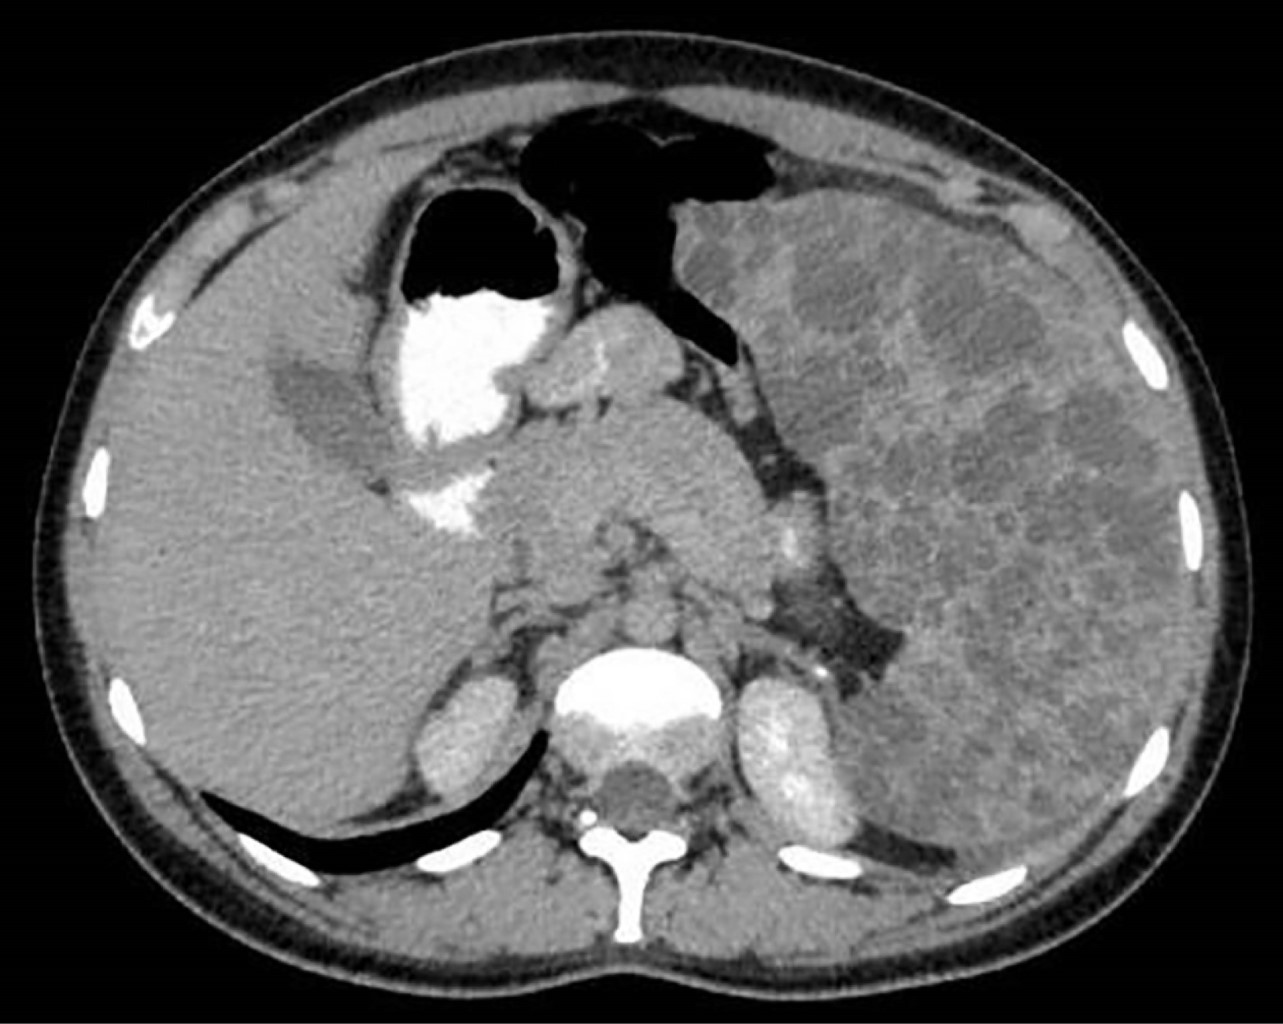

Presentamos el caso de una mujer de 27 años de edad sin antecedentes cronicodegenerativos ni quirúrgicos de importancia. Inició su padecimiento de un mes de evolución, con presencia de cefalea leve, malestar al comer y náuseas, por lo que acudió a valoración médica no especializada. Se prescribe una ecografía abdominal que reporta un tumor esplénico como hallazgo principal. Es referida a consulta médica de especialidad en cirugía general. A la exploración física se encontró abdomen globoso a expensas de visceromegalia, blando, pero no depresible en cuadrante superior y flanco izquierdos, no doloroso, sin datos de irritación peritoneal, extremidades íntegras, con hipotonía en extremidad pélvica izquierda y presencia de hemangioma subcutáneo en miembros pélvicos, sin limitación en los arcos de movimiento. Se realizaron estudios de laboratorio que reportaron de relevante sólo anemia leve (11.6 g/dL) y leucopenia (3.2 × 109/L). La tomografía de abdomen simple reportó esplenomegalia severa, con múltiples imágenes nodulares e hiperdensas, asociado a heterogeneidad del plano graso peritoneal del interior del hueco pélvico, observando imágenes nodulares hiperdensas sugerentes de tejido ganglionar calcificado (Figura 1). Se decidió programar a la paciente para esplenectomía laparoscópica mano asistida por el tamaño del tumor, previo protocolo quirúrgico completo se ingresó a paciente a quirófano, se inició procedimiento, con abordaje laparoscópico abierto, supraumbilical y en línea media con incisión de 8 cm disecando por planos hasta la cavidad, bajo visión directa se colocaron trocares de trabajo, disección mano asistida de hilio esplénico y las fijaciones ligamentosas con energía ultrasónica y bipolar avanzada presentando hemostasia difícil debido a las dimensiones del bazo. Se colocaron Hem-O-Locks proximales y distales, así como clips de titanio, obteniendo hemostasia, se introdujo pieza quirúrgica en bolsa extractora, y se extrajo de la cavidad peritoneal mediante morcelación manual, sin complicaciones, se verifica hemostasia y limpieza de cavidad con 3 litros de solución estéril (Figura 2). Se retiraron trócares y se afrontaron incisiones por planos. La paciente se mantuvo con evolución favorable durante su estancia hospitalaria, sin referir ninguna sintomatología, se egresó al tercer día del periodo posquirúrgico. El resultado de patología reportó bazo multifragmentado y deformado, 33 × 20 × 8 cm de tamaño, peso de 1,180 gramos, con linfagioma esplénico difuso, áreas de parénquima esplénica con esplenitis crónica con congestión y dilatación vascular (Figuras 3, 4 y 5). Se continuó con seguimiento por la consulta externa a los siete y 21 días de la cirugía con evolución favorable. Al día 10 se sometió a doble esquema de vacunación contra Streptococcus pneumonie (Neumococo) y Neisseria meningitidis (Meningococo) sin eventos adversos.

Figura 1